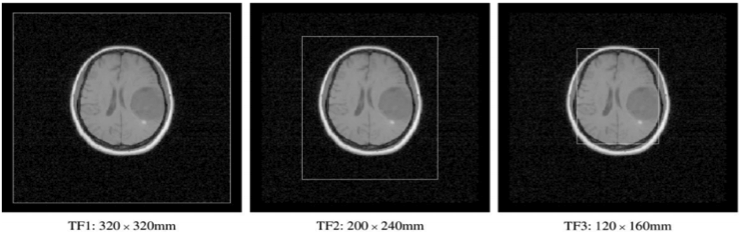

2.3.2 Capture Range Experiment

The aim of these experiments was to examine the behavior of the registration algorithm using different measures when it is presented along with clinical data with varying fields of view. In this case we concentrated on recovering rigid registration parameters as the trans-axial field of view. Varying the in-plane field of view determines the proportion of the image exhibiting values corresponding to air in the two modalities. In order to look at the effect this has on the registration measures; an image set (patient 5 of the Vanderbilt study) was be truncated in-plane at three levels to produce three pairs of images to register. The fields of view selected (labeled TF1, TF2 and TF3) in the MRI, CT and PET images are shown in Figure 2.

To examine how robustly different levels of initial misalignment may be recovered using the measures, sets of randomized starting estimates were produced. In these experiments sets of randomized transformations were used. These were derived by perturbing the rigid marker based parameters with random translations and rotations of sizes (mm, ),(mm, ), and (mm, ). These were then used as starting estimates for the optimization algorithm in each of the three measurements.